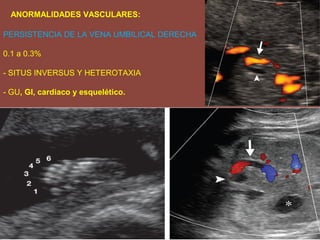

ANORMALIDADES VASCULARES:

PERSISTENCIA DE LA VENA UMBILICAL DERECHA

0.1 a 0.3%

- SITUS INVERSUS Y HETEROTAXIA

- GU, GI, cardiaco y esquelético.

ANORMALIDADES VASCULARES: PERSISTENCIA DELA VENA UMBILICAL DERECHA 0.1 a 0.3% - SITUS INVERSUS Y HETEROTAXIA - GU, GI, cardiaco y esquelético.